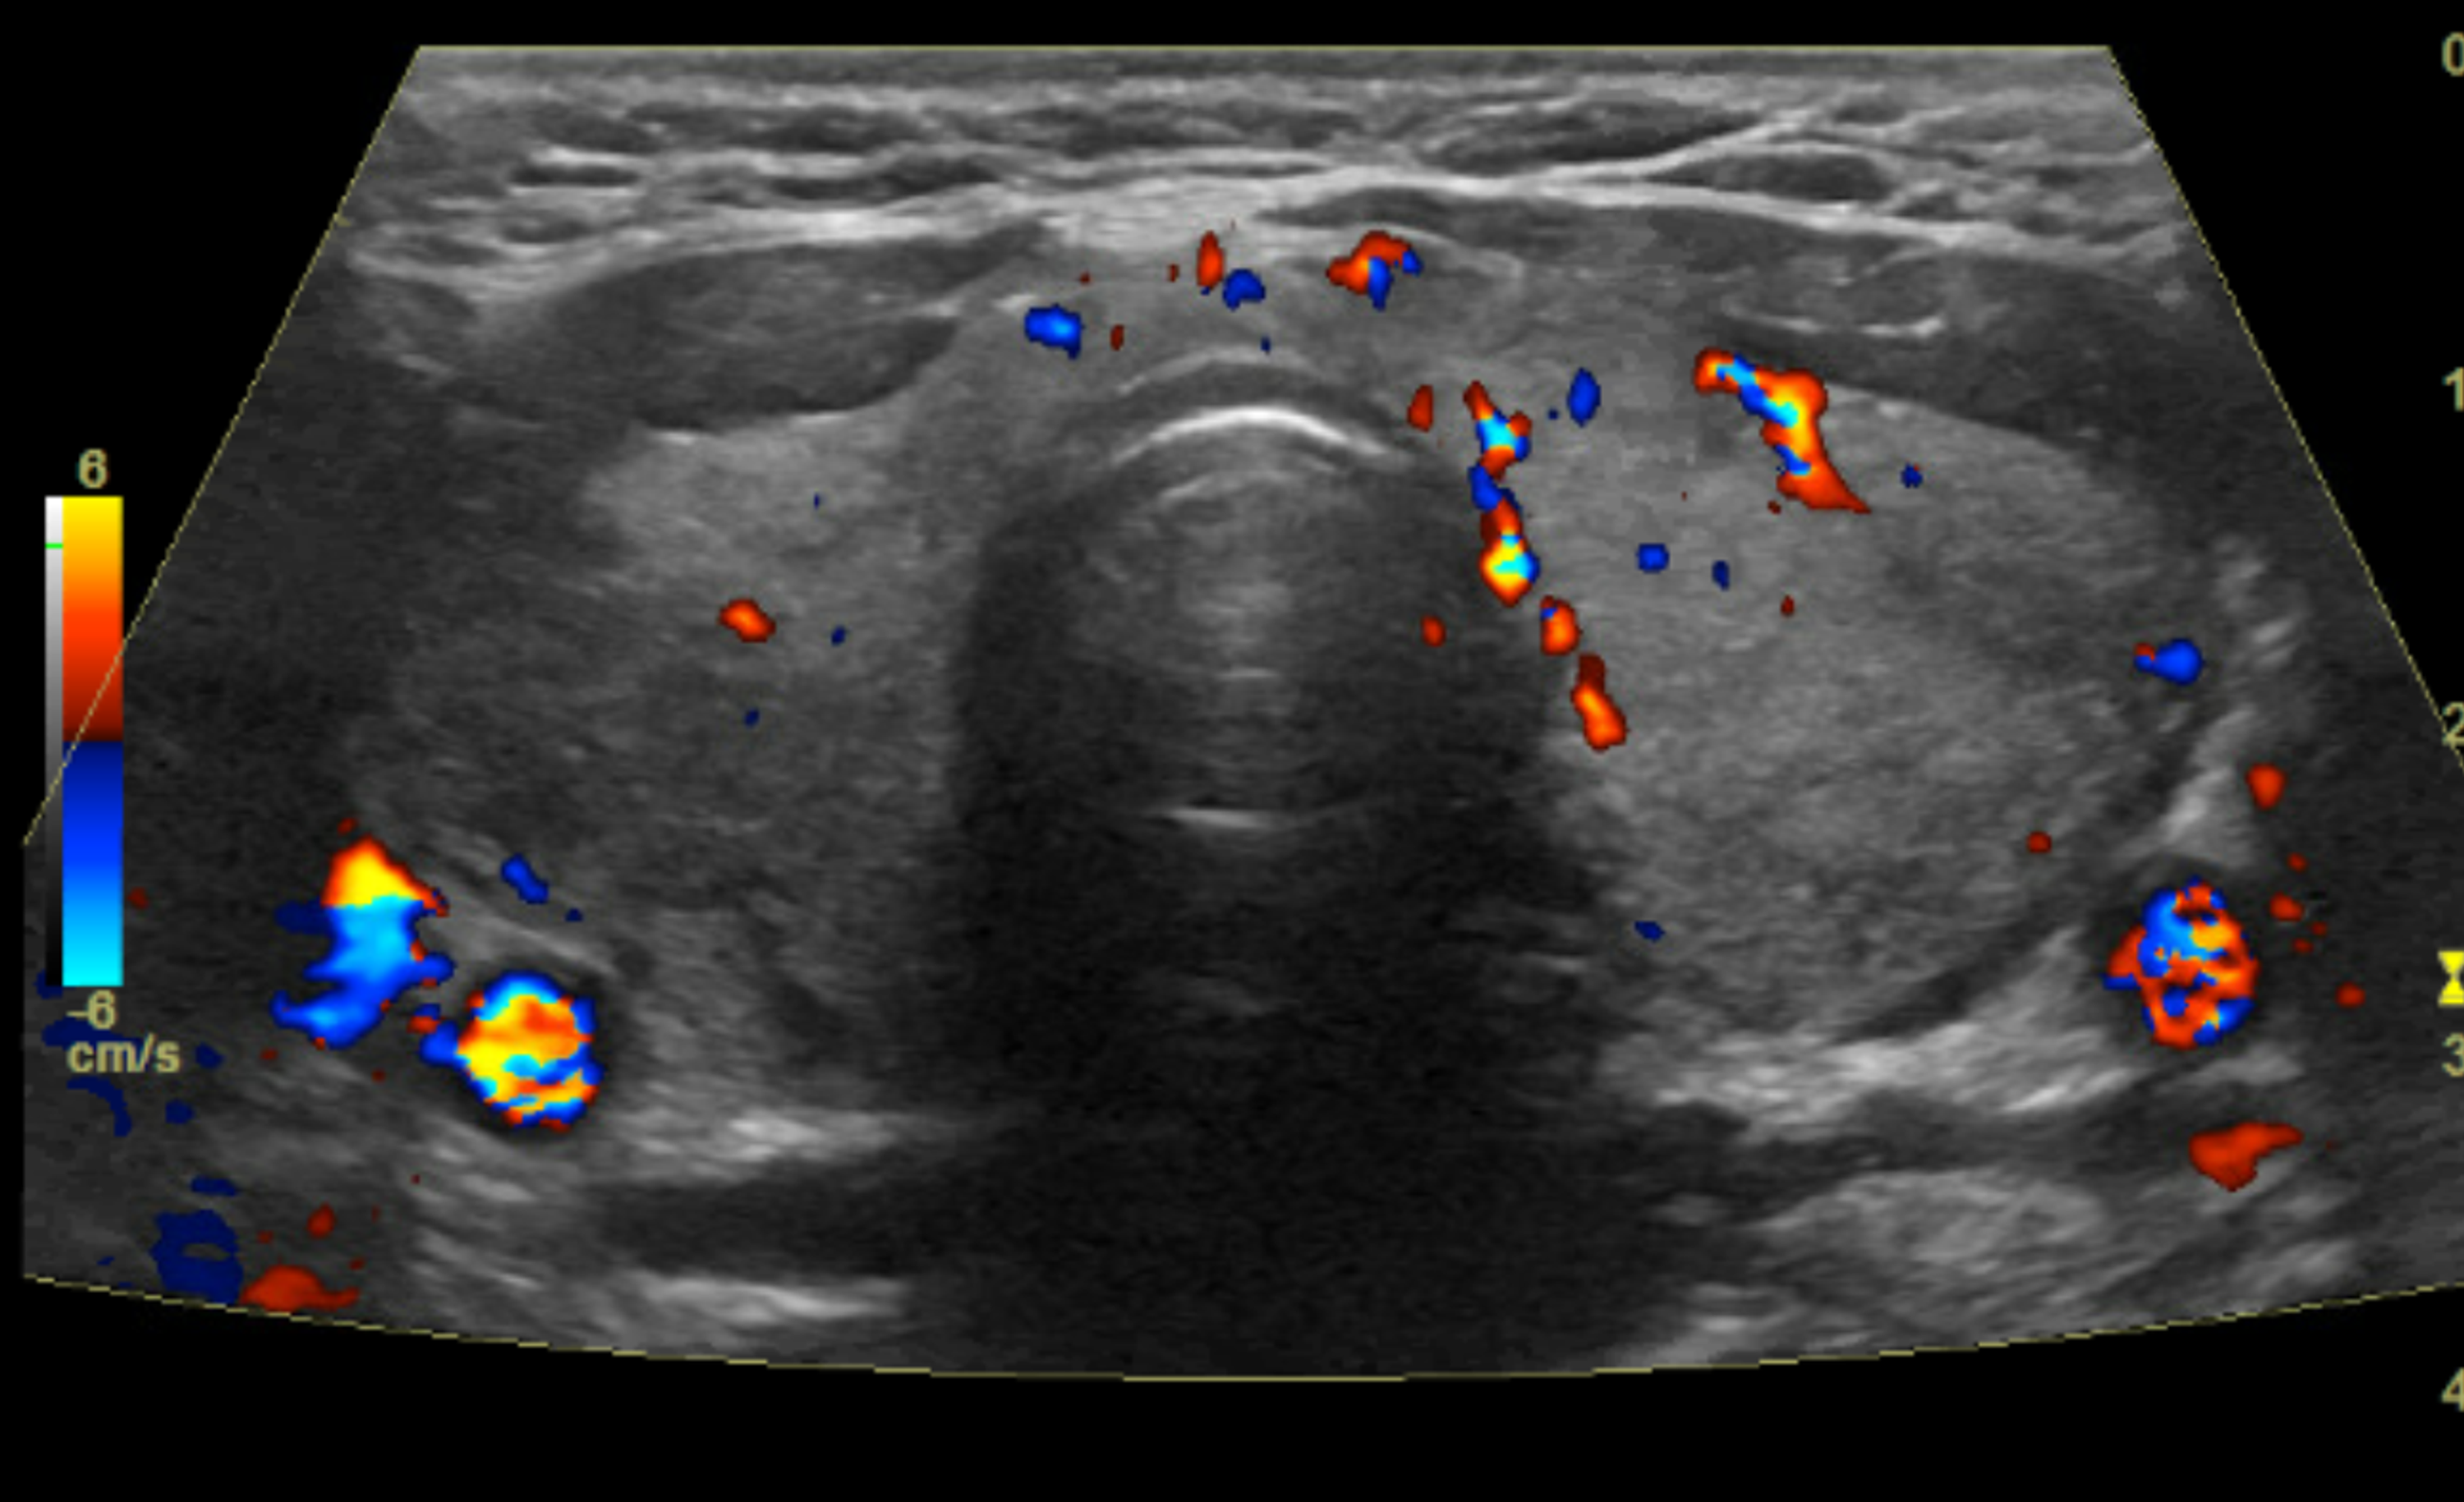

[PDF] Graves' Disease Thyroid ColorFlow Doppler Ultrasonography What Does Graves Disease Look Like On Ultrasound graves’ disease (gd) is an autoimmune disorder which recognizes. graves’ disease is an autoimmune condition where your immune system creates antibodies called thyroid. ultrasound guidance is used to perform thyroid biopsies and improves the diagnostic accuracy of fine needle biopsy. there are quite a few important points to take into consideration (i) coexistence of nodules in. What Does Graves Disease Look Like On Ultrasound.

What Does Graves Disease Look Like On Ultrasound . graves’ disease (gd) is an autoimmune disorder which recognizes. ultrasound guidance is used to perform thyroid biopsies and improves the diagnostic accuracy of fine needle biopsy. graves’ disease is an autoimmune condition where your immune system creates antibodies called thyroid. A thyroid gland impacted by graves’ disease is often enlarged and may have increased blood flow; the cardinal sonographic features of graves’ disease 6, 22 are mild to moderate diffuse and symmetrical. there are quite a few important points to take into consideration (i) coexistence of nodules in graves’ disease is quite.

A thyroid gland impacted by graves’ disease is often enlarged and may have increased blood flow; there are quite a few important points to take into consideration (i) coexistence of nodules in graves’ disease is quite. the cardinal sonographic features of graves’ disease 6, 22 are mild to moderate diffuse and symmetrical. ultrasound guidance is used to perform thyroid biopsies and improves the diagnostic accuracy of fine needle biopsy. graves’ disease (gd) is an autoimmune disorder which recognizes. graves’ disease is an autoimmune condition where your immune system creates antibodies called thyroid.